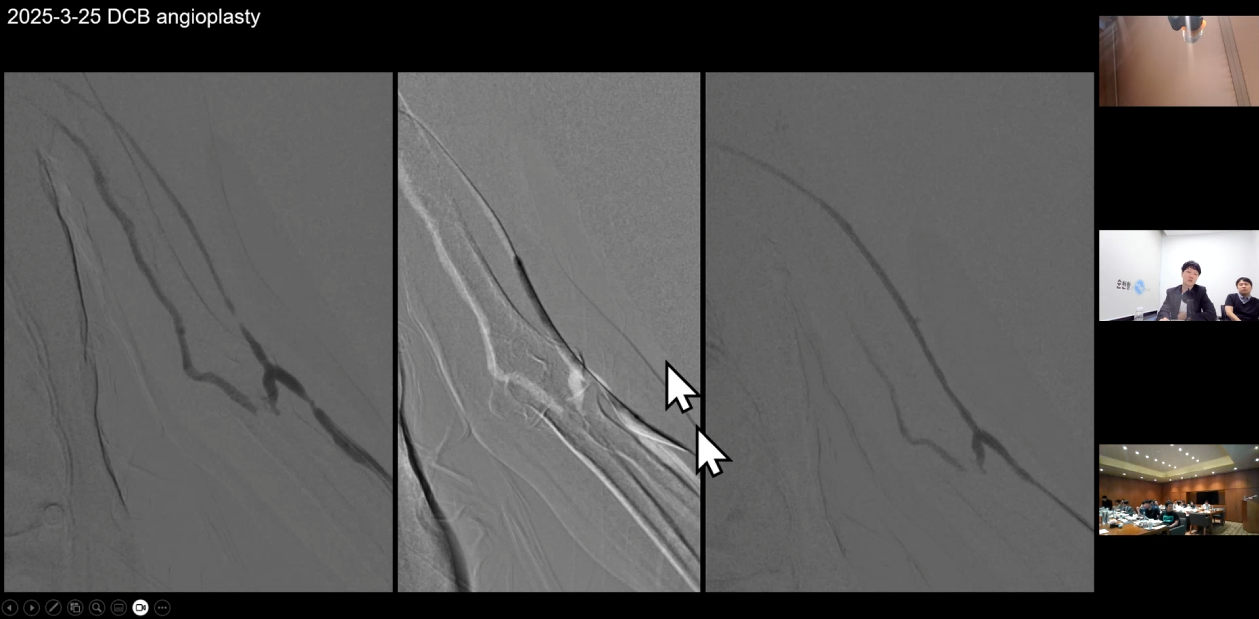

권요한 원장님은 'Can a DCB be a GAME changer?'라는 주제로

DCB에 대한 문헌 검토와

투석혈관 치료에서 DCB가 어떻게 사용되는지

시술 사례와 함께 치료 전략을 공유했습니다.